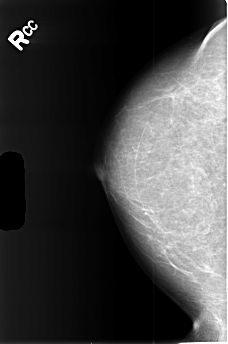

B_3444_1.RIGHT_CC

RIGHT_CC LINES 4464 PIXELS_PER_LINE 2960 BITS_PER_PIXEL 12 RESOLUTION 50 NON_OVERLAY